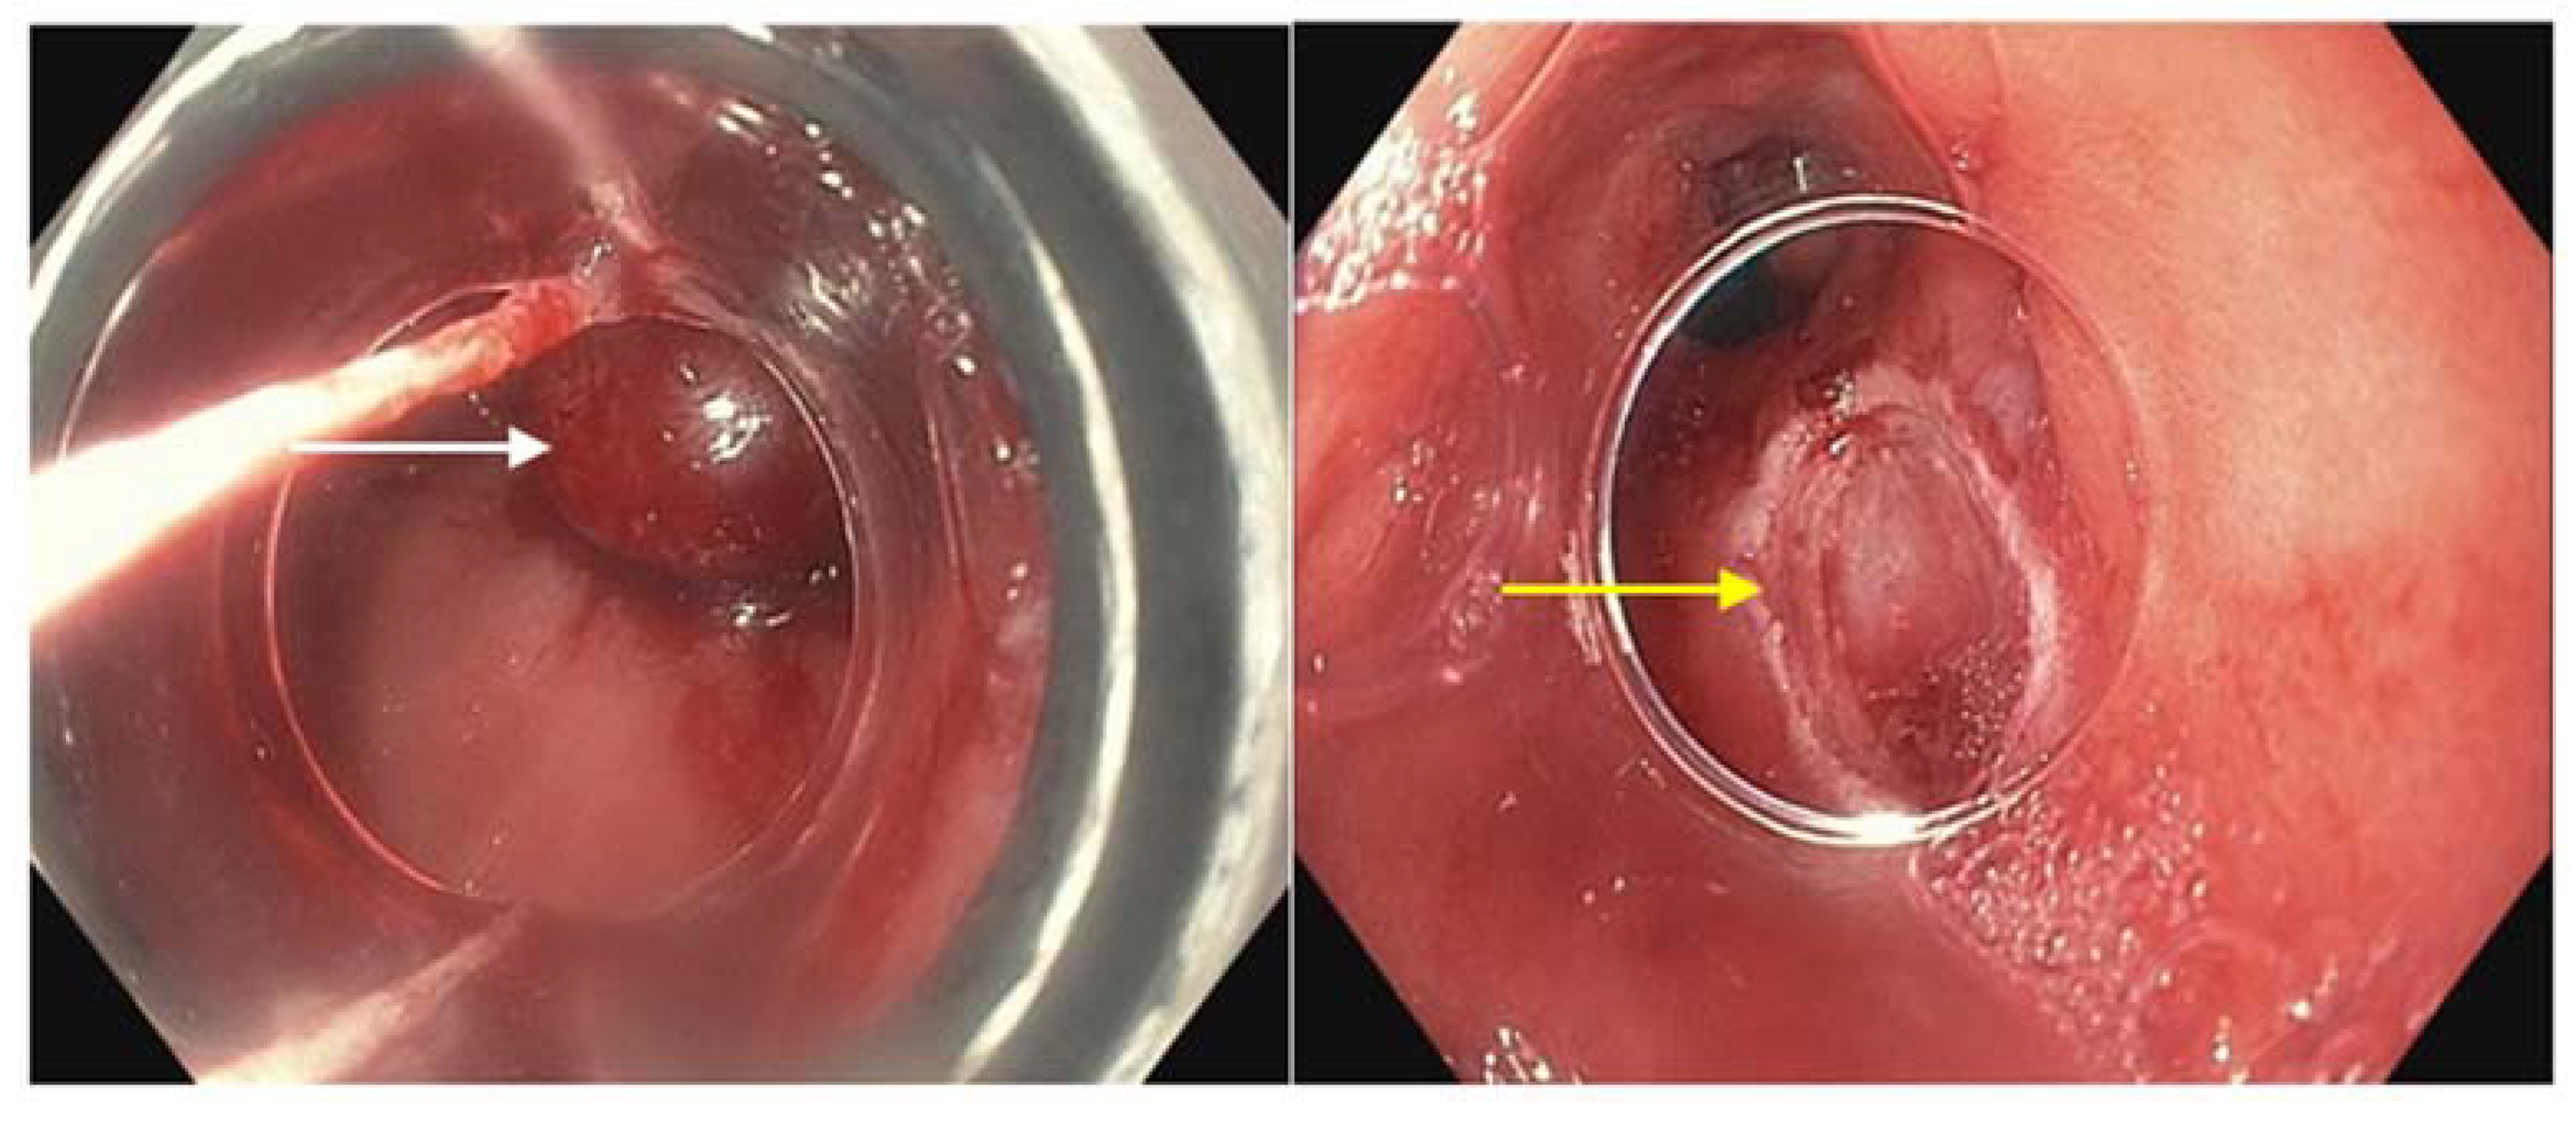

Radiofrequency ablation (RFA) (Figure 3) can be employed to eradicate circumferential areas of dysplastic BE. It is often used in conjunction with EMR for complete diagnosis and treatment; nodular BE requiring EMR for appropriate resection and non-nodular BE benefiting from targeted or focal ablation. When required for complete eradication following initial EMR or EMR with RFA, serial RFA is typically performed every 3 months [81,82].

Figure 3.

Radiofrequency ablation being applied using a probe toa dysplastic mucosal area (white arrow).

RFA has been shown to be highly effective in completely eradicating intestinal metaplasia and all grades of dysplasia and neoplasia, and on average required 3–4 treatment sessions for eradication [81]. Pooled CE-IM rates of 78% and rate of complete eradication of dysplasia (CE-D) of 91% [82]. It was found that pre-treatment histology was a non-significant determining factor in efficacy, with LGD more likely to demonstrate CE-IM and CE-D than HGD and/or intramucosal cancer [82]. Characteristics associated with incomplete eradication included BE segment length, incomplete healing between serial RFA therapy, and requirement of more treatment sessions [81]. RFA treatment failure can be difficult to define by threshold number of treatment sessions given that cases have been successfully eradicated following more than four or five sessions. RFA is widely accepted as first-line therapy given efficacy and safety; however, adverse effects can include, most commonly, strictures, bleeding, and pain.